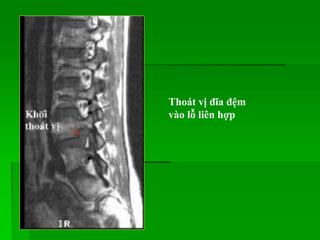

Thoát vị đĩa đệm

vào lỗ liên hợp

Thoát vị đĩađệm vào lỗ liên hợp